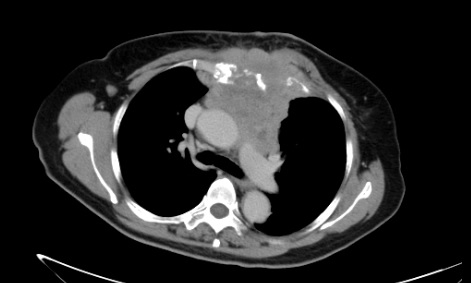

乳腺癌纵隔及胸壁转移氩氦刀冷冻消融联合放射性粒子植入治疗前、中、治疗后对比

经过冷冻消融、碘-125放射性粒子植入术,并4个周期全身化疗后,病灶明显缩小。祁阿姨原本确诊时沉重心终于如释负重,阿姨久违的笑容再次出现了。